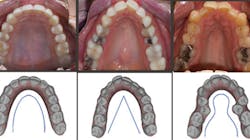

If we take the time to disclose the cause of disease, we can then focus on proper treatment modalities. The root cause of most crowded malocclusions is a result of three conditions: improper arch form, improper arch width, and improper buccolingual inclination (figure 1).

Figure 1: Examples of a proper U-shaped arch (left), an improper V-shaped arch (middle), an improper omega-shaped arch (right). Photos courtesy of Dr. Ben Miraglia.

Figure 3: 36 mm is an appropriate width; the others display improper width and insufficient tongue space. Photos courtesy Dr. Ben Miraglia.

36 mm

30 mm

32 mm

25 mm

As the transverse measurement decreases, so does the “home” for the tongue. In Figure 3, you notice the narrowing of the arch and the increased vault of the palate in direct proportion to the decreasing width of the transverse (McNamara) measurement.